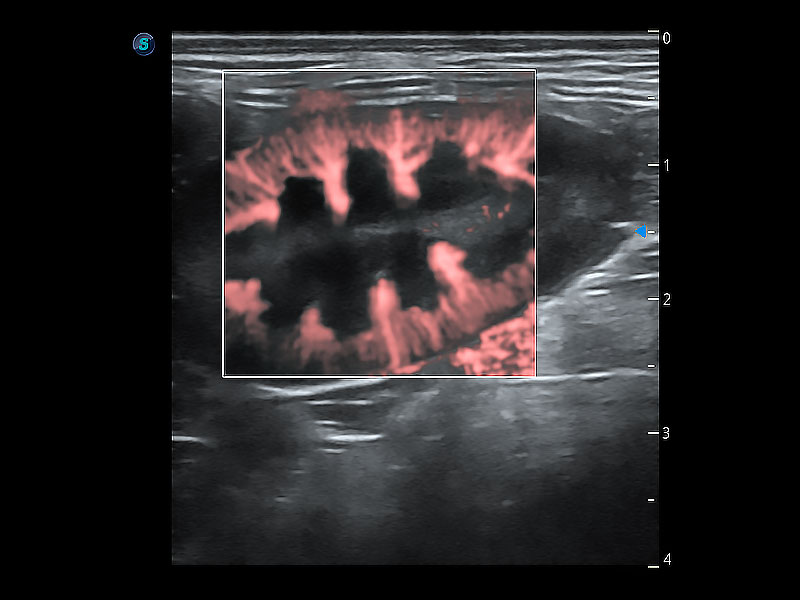

• Micro F 显微血流成像

极大提升超低速微细血流的检出能力,同时更精准地滤除软组织和超声信号,为兽用医生提供以往无法通过常规血流获得的疾病诊断信息。

(犬)肾脏显微血流